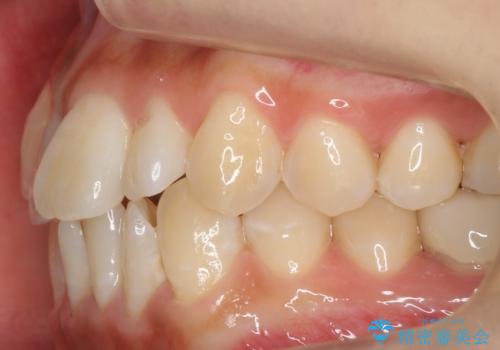

八重歯をインビザラインで 抜歯矯正

- 八重歯を主訴に来院。

出来るだけワイヤー矯正を避け、抜歯も最小限の本数をご希望でした。

下の前歯のみ1本抜歯しています。

下の前歯の周りの骨は薄いことが多く、無理に並べると唇側の骨がやせて歯ぐきが下がり歯が長く見えます。

それを回避するために今回は下顎前歯を一本抜歯をしています。